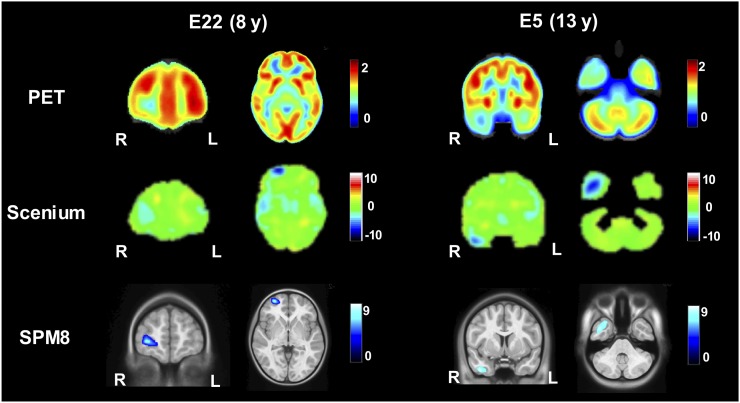

Figure 3 compares the voxelwise statistical maps obtained for two representative patients. In both patients, SPM8 correctly detected the presumed epileptogenic areas located in the right frontal lobe and right temporal lobe, respectively, as reported by the MDT diagnosis. These regions were also highlighted in the z score maps from Scenium. However, despite being visible on the maps, these regions did not reach the significance threshold of less than −2 SDs in the region-of-interest–based statistical tables, considered for clinical reporting. Indeed, for patient E22, the most hypometabolic region was found in the left temporal lobe, with −3 SDs, whereas the right frontal lobe had only −0.3 SDs. In the case of patient E5, the most hypometabolic region, with −2.3 SDs, was placed in the left parietal region, whereas the right temporal lobe resulted in −1.0 SDs.

FIGURE 3.

Comparison of voxelwise statistical maps of Scenium (z score) and SPM8 (t value). Two representative slices (from patients E22 and E5) approximately at same anatomic level were chosen, considering the different size of standard spaces within Scenium and SPM8.